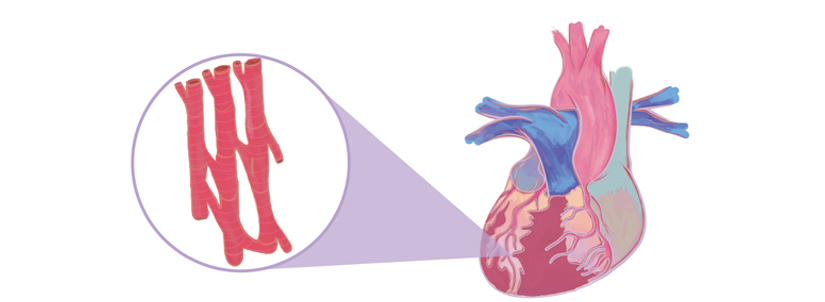

Cardiomyocytes

Cardiomyocytes make up the striated heart muscle. Unlike skeletal muscle cells, cardiomyocytes have a branching morphology.